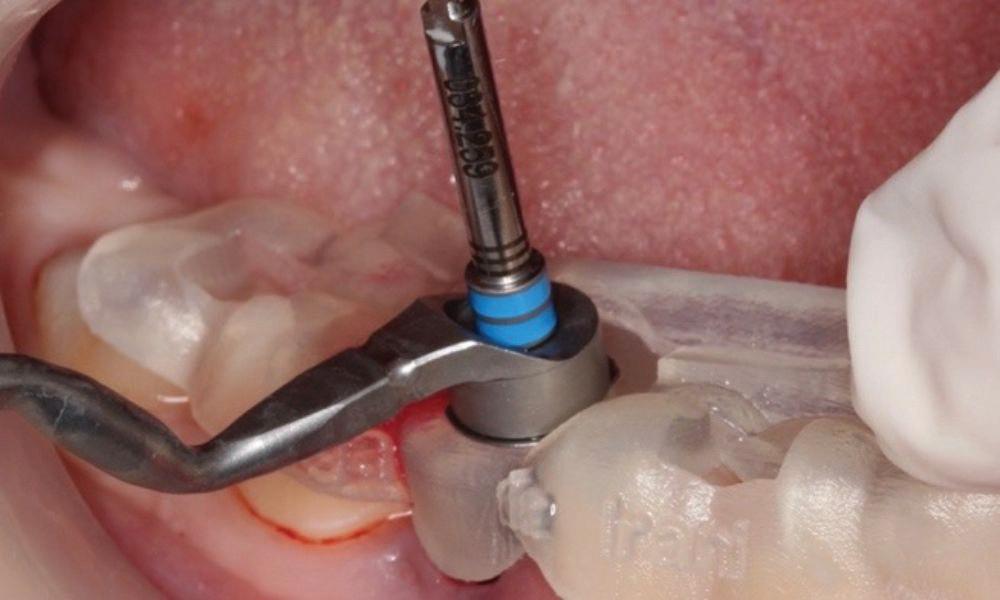

Clear radiographs are essential to accurate diagnosis and are a special test that dentists per form regularly many times throughout the day. Following the ALARA principle, we want to ensure we take a minimal number of radio graphs to ensure low radiation dosage so to repeat radiographs due to operator error should be avoided. The use of film holders allow the clinician to visualise how the radiographs should be taken to optimise the clarity of the image and ensure the diagnostic value of the image. Hawe Solutions x-ray film holders...

Figure 1: Radiographic Image of implants do not demonstrate bone loss due to the bisecting angle of the radiograph taken.

Figure 2: Radiographic image in a paralleling technique of implants dem onstrate moderate peri-implantitis with bone loss that will necessitate treatment.

• Allow exact posi tioning of the film or phosphor plate relative to the tooth - no bending and thus no distortion;

• Require no guesswork - exclusive, automatic reliance on the extraoral aiming and centring device;

• Deliver semi-reproducible images (quasi standardisation)the use of film holders allows some sense of reproducibility for assessment over time; and

• Produce optimally clear radiographs.